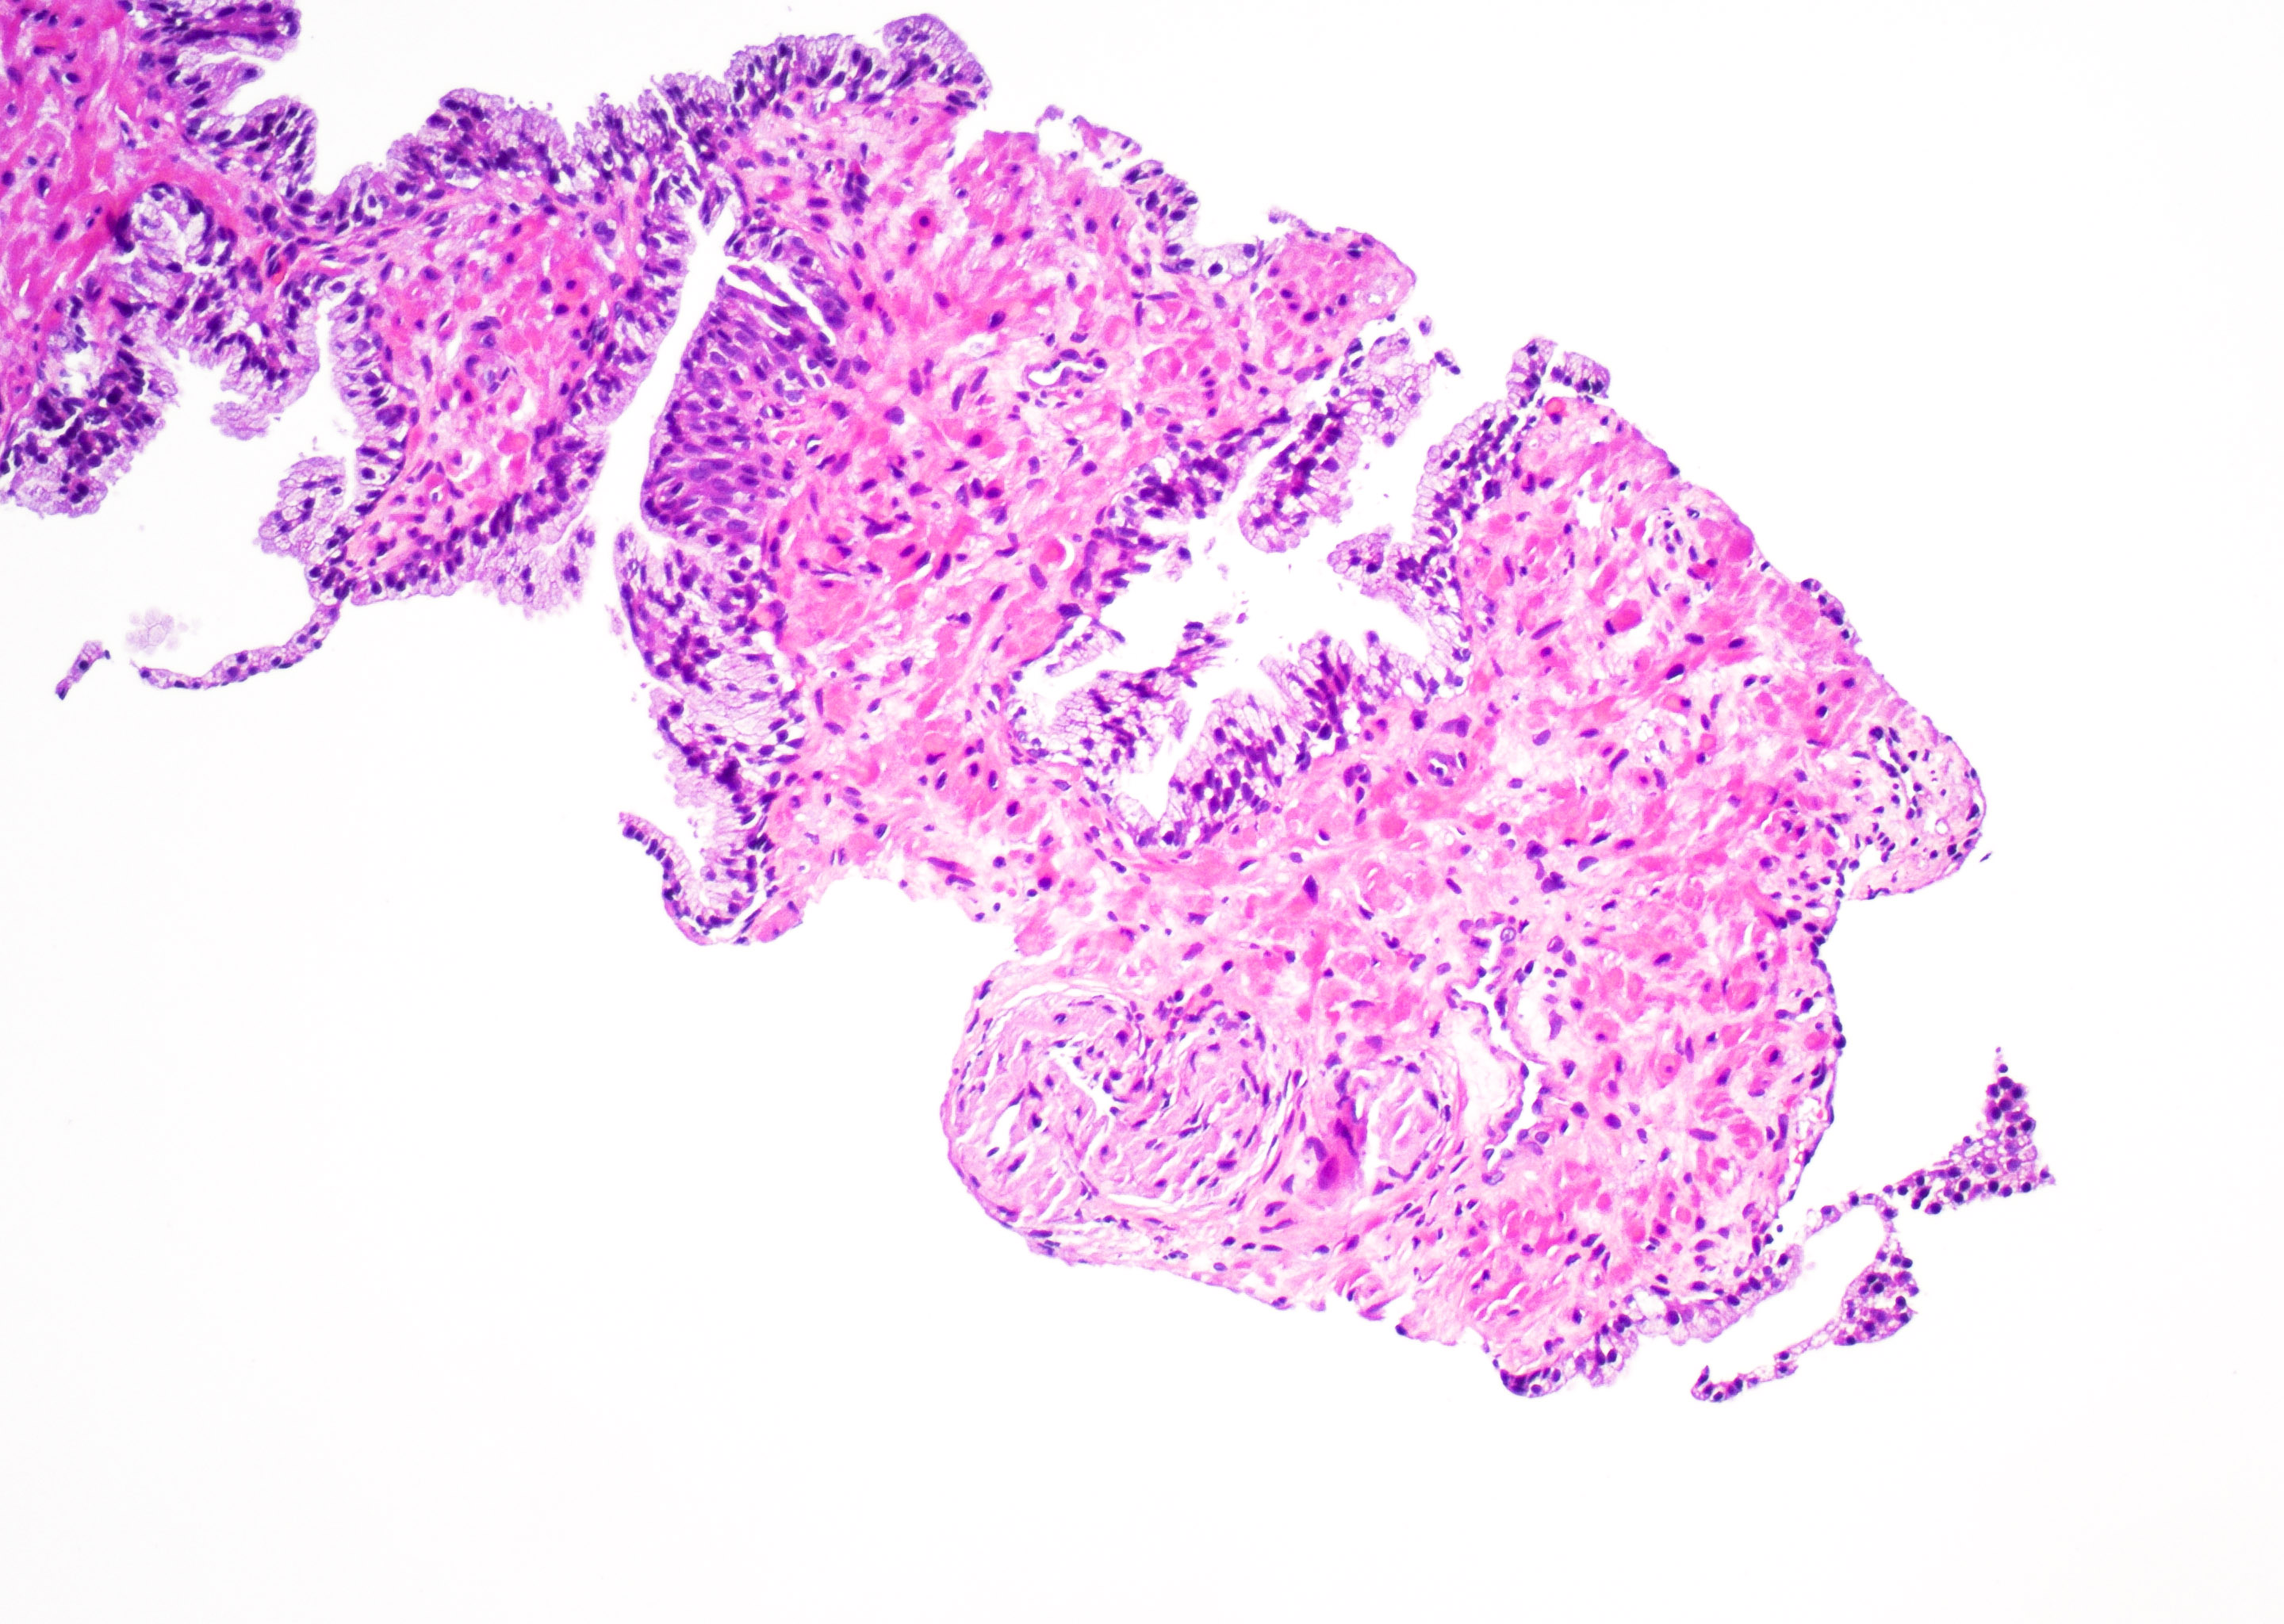

Vulvar skin biopsy. Erythematous pruritic eruption. Your diagnosis?

Only H&E stain needed for this one!